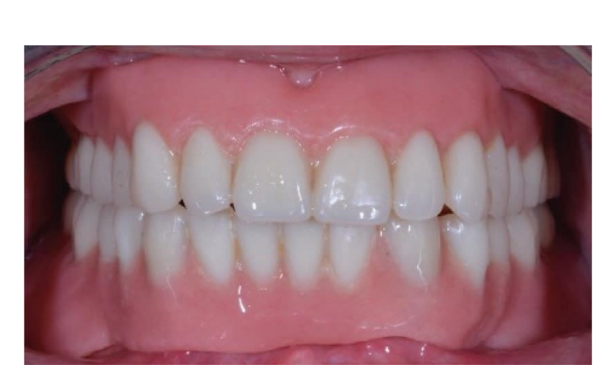

Dopo l'intervento, ai pazienti è stato consigliato di evitare qualsiasi trauma nel sito chirurgico, comprese le procedure di spazzolamento. È stata prescritta una dieta fredda e morbida post-chirurgica. Dopo l'intervento, ai fumatori è stato consigliato di astenersi dal fumo per due settimane. Sono state fornite istruzioni dettagliate per l'igiene orale, inclusa la raccomandazione di sciacquare tre volte al giorno con clorexidina allo 0,12%. Sono stati prescritti analgesici, come 600 mg di ibuprofene o alternative simili, secondo necessità. I punti di sutura sono stati tipicamente rimossi entro un periodo di dieci a quattordici giorni. Secondo un flusso di lavoro precedentemente riportato, le procedure protesiche sono iniziate otto settimane dopo l'inserimento degli impianti. Secondo un protocollo di carico precoce, una nuova dentiera rimovibile completa rinforzata in metallo è stata consegnata in entrambi i gruppi entro quattro settimane dopo l'inserimento degli impianti. Dopo due o tre giorni, gli abutment di guarigione sono stati svitati e gli attacchi sono stati collegati a lato della poltrona alla nuova protesi rimovibile. I pazienti sono stati randomizzati per ricevere attacchi OT Equator® (Rhein’83, Bologna, Italia) nel gruppo di test o attacchi Locator (Zest Anchors LLC) nel gruppo di controllo. I sistemi di attacco randomizzati sono stati posizionati e serrati secondo le istruzioni del produttore. Nel gruppo di test (Figure 1–5), dopo la guarigione gengivale, i più recenti attacchi OT Equator® a basso profilo sono stati avvitati sugli impianti utilizzando il cacciavite quadrato OT Equator®, con un intervallo di coppia di 22–25 Ncm. Le altezze dei manicotti variavano da 0,5 a 7,0 mm, a seconda delle dimensioni della zona di transizione di ciascun impianto, facilmente misurabili utilizzando il misuratore di altezza del manicotto millimetrico a codifica colore (Rhein’83, Bologna, Italia) dopo la rimozione dell'abutment di guarigione. Successivamente, è stato preparato lo spazio necessario per accettare la gabbia in acciaio della sede femminile nella superficie di adattamento della dentiera rimovibile completa mandibolare. Dischi protettivi in silicone (Rhein’83, Bologna, Italia) sono stati posizionati sopra gli attacchi OT Equator®. Cappucci di ritenzione extra-morbidi (giallo, 600 g) sono stati inizialmente inseriti nella sede femminile in acciaio, attaccati a OT Equator®, e infine fissati alla dentiera utilizzando resina acrilica autoindurente. Allo stesso tempo, il paziente ha tenuto le dentiere in occlusione, direttamente a lato della poltrona. Dopo la completa polimerizzazione, la dentiera è stata prelevata e i dischi in silicone sono stati rimossi. L'eccesso di acrilico è stato rifilato e la dentiera è stata rifinita e lucidata. Un mese dopo la consegna delle protesi, i cappucci di ritenzione gialli sono stati sostituiti con un tipo più robusto (rosa, 1200 g).